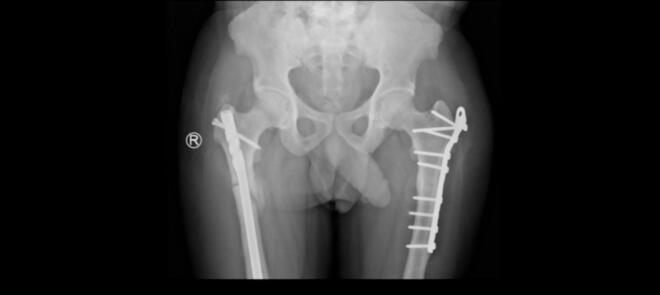

We present a 45-year-old male with adult-onset autosomal dominant osteopetrosis who sustained bilateral subtrochanteric femoral fractures-first on the right side, then on the left two years later. Both fractures were managed with intramedullary nailing (IMN). The procedures were technically demanding due to the sclerotic bone and canal obliteration, requiring sequential drilling and reaming with irrigation to prevent thermal necrosis. Both fractures healed without complications, with radiographic union at 9 months and early mobilization.

我们报告一名45岁成年男性,患常染色体显性遗传性成人骨质石化症,双侧股骨转子下骨折——右侧先发生骨折,两年后左侧发生骨折。两处骨折均采用髓内钉固定(IMN)治疗。由于骨质硬化和髓腔闭塞,手术操作技术要求高,需要依次钻孔、扩髓并冲洗以防止热坏死。两处骨折均愈合且无并发症,9个月时影像学显示骨折愈合,并可早期活动。